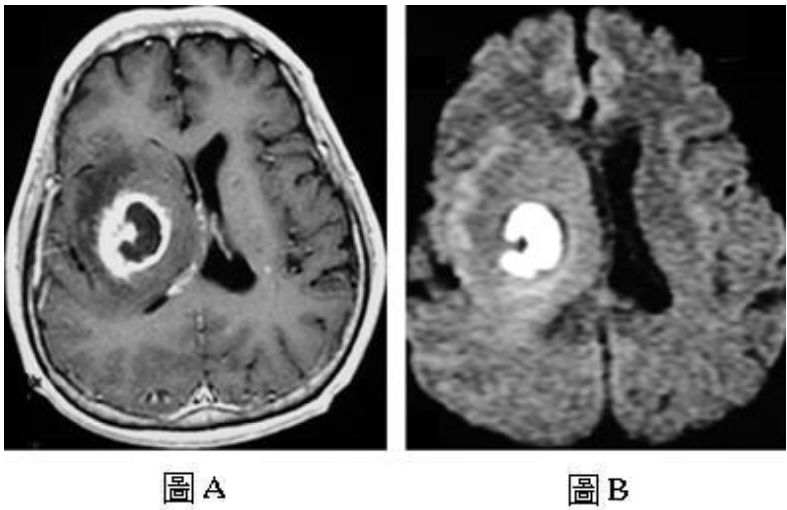

75.50歲男性患者,主訴左側肢體無力已經二個星期,接受磁振造影檢查,圖A是注射顯影劑後的T1加權影像, 圖B是擴散加權影像(diffusion-weighted image),下列何者是最可能的診斷? (A)多型性神經膠母細胞瘤(glioblastoma) (B)細菌性膿瘍(pyogenic abscess) (C)轉移(metastasis) (D)多發性硬化症(multiple sclerosis)